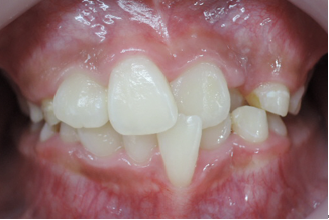

歯並びの悪い症例

前歯がクロスしていて将来、口腔機能に悪影響を及ぼす事となります。

①前歯のクロスを改善するためには咬み合わせを高くする必要があります。

当矯正歯科医院では上顎の乳臼歯にレジンを盛る事で、クロスした前歯の被蓋(前歯の咬み合わせ)を改善していきます。

前歯のクロスが改善されて治療しやすくなっています。

その後、ブラケット装着を使用して上顎骨の拡大を始めます。